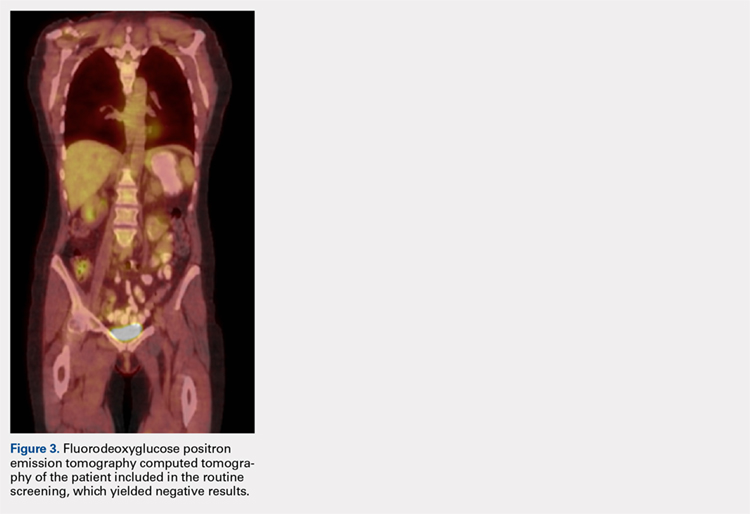

MRI of the foot and ankle was reviewed and demonstrated a large soft-tissue mass over the medial aspect of the ankle extending posteriorly to engulf the medial flexor tendons and medial neurovascular bundle (Figures 2A-2C). Interestingly, the radiologist’s report only mentioned a “large region of devitalized tissue underlying the known medial ankle ulcer which extended to the tibiotalar and subtalar joints and bone marrow changes in the talus most compatible with osteomyelitis.” FDG PET-CT images from the patient’s past 2 years were reviewed, and the radiologist was contacted to confirm the negative findings. Unfortunately, FDG PET-CT performs no routine imaging below the elbow or knee when evaluating for this particular malignancy (Figure 3).At presentation, our differential diagnosis included recurrence of the malignancy, secondary malignancy, infection, and inflammatory disease. After a lengthy discussion with the patient and consultation with our institution’s musculoskeletal oncologist, the decision was made to perform a right-ankle mass biopsy and marginal excision with wound irrigation and débridement and tarsal tunnel release.